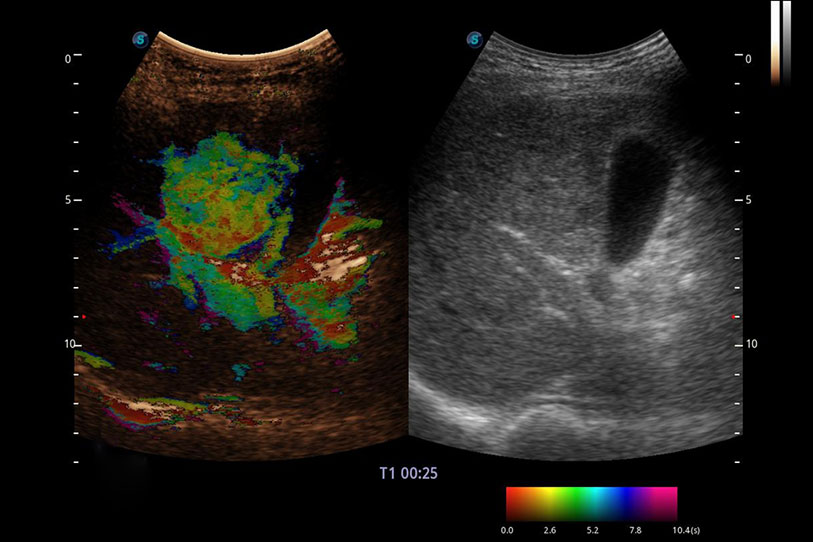

采用紅、橙、黃、綠、青、藍(lán)、紫這七種肉眼最為敏感的色彩,直觀(guān)地顯示組織內(nèi)血流灌注的時(shí)間先后信息,更精準(zhǔn)捕捉血流灌注走行細(xì)節(jié)。